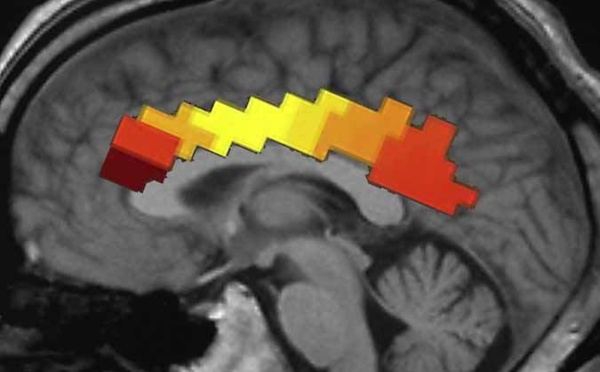

Determinan el grado de conciencia de pacientes en coma con un simple escáner - 14/10/2013

¿Qué ocurre en la mente de personas aparentemente inconscientes que no se pueden comunicar? ¿Se debe descartar cualquier atisbo de conciencia en ellas? Para aclarar estas cuestiones, un equipo de científicos del ICM francés ha diseñado una medida que determina el grado de actividad neuronal de este tipo de pacientes. Y lo hace de manera sencilla, con una herramienta rutinaria: un escáner situado junto a sus camas.